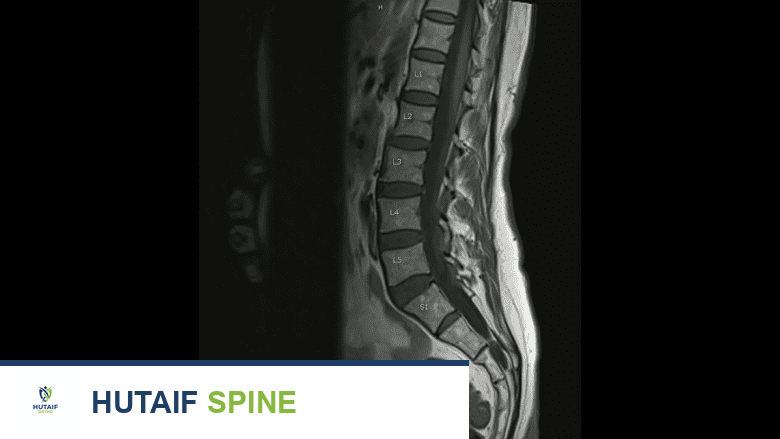

صورة بالأشعة المقطعية لفقرة قطنية.

تُقدم فحوصات الرنين المغناطيسي صورًا تفصيلية للأنسجة الرخوة، بما في ذلك الأعصاب والأقراص المحيطة بالكسر.

3. التصوير بالرنين المغناطيسي (MRI Scan):

• قد يُطلب التصوير بالرنين المغناطيسي إذا اشتبه الأستاذ الدكتور محمد هطيف في وجود سبب آخر لألم المريض (مثل انزلاق غضروفي)، أو إذا كان هناك احتمال لتأثر الأعصاب القريبة من الكسر.

• يُظهر التصوير بالرنين المغناطيسي مستوى عالٍ من التفاصيل للأنسجة الرخوة (مثل الأعصاب والأقراص) المحيطة بالكسر والتي قد تتأثر.

• ميزة فريدة: يمكن للتصوير بالرنين المغناطيسي أيضًا تحديد ما إذا كان الكسر قديمًا أم حديثًا. في الكسر الحديث، ستظهر العظام داكنة بشكل خاص في تسلسل معين من الصور (الصور السهمية الموزونة T1). هذه المعلومة حاسمة لتوجيه خيارات العلاج.